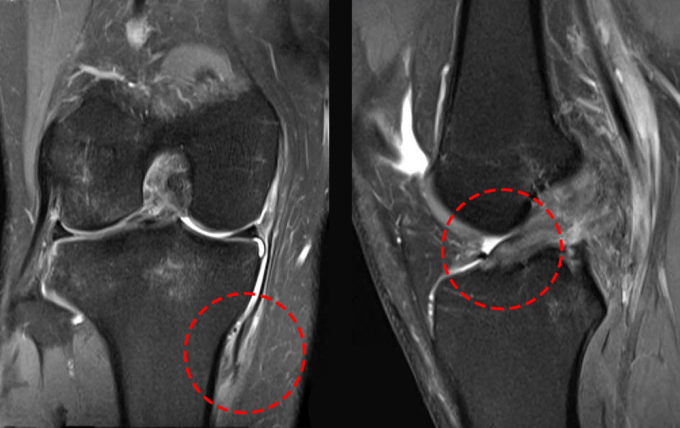

ThS.BS Vũ Trung Hiếu, Khoa Chấn thương Chỉnh hình, Bệnh viện Đa khoa Tâm Anh Hà Nội, kiểm tra bằng nghiệm pháp ép vẹo ngoài khớp gối người bệnh cho kết quả dương tính ở khoảng gấp 30 độ, đặc trưng của tình trạng đứt dây chằng bên trong (MCL). Kết quả chụp cộng hưởng từ (MRI) xác nhận dây chằng bên trong gối phải đứt tại điểm bám xương chày, kèm đứt dây chằng chéo trước (ACL), rách sụn chêm ngoài.